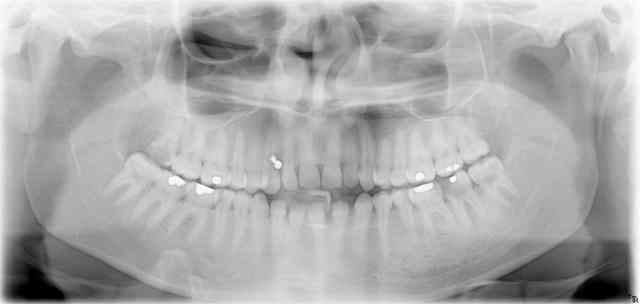

Sur ce, je vais essayer de me motiver pour mon prochain patient dont voici la pano.

PS: depuis que je le traite, je progresse nettement en endo

PPS: il est effectivement CMU celui-là et il a 26 ans...

"Cmu du soir espoir"

Sinon, je ne comprends pas: je ne vois pas beaucoup d'endos à faire ici, mais des extractions, là oui!

Au fait dis donc tu soignes dans quel coin pour avoir des GIG (rescapés de Guerre) comme ça?

Verdun? Waterloo? La Marne?